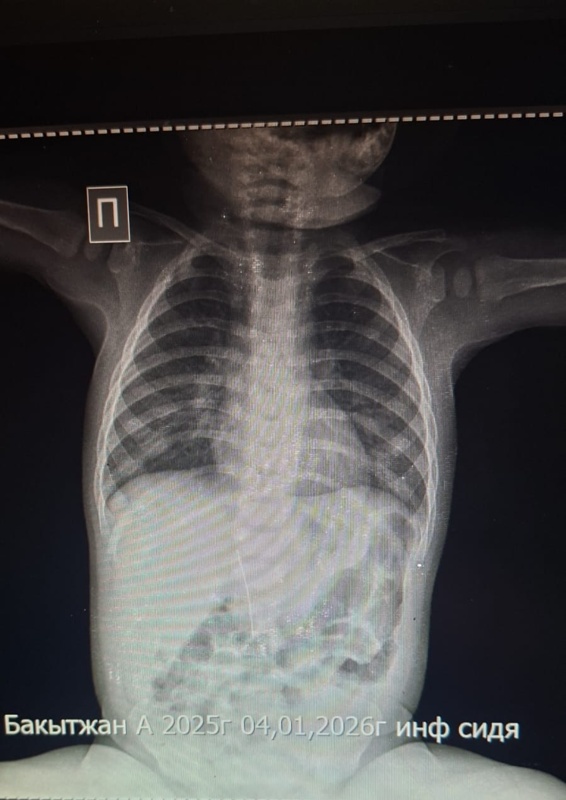

Во время рентгенологического исследования врачи обнаружили в брюшной полости восьмимесячного малыша инородный предмет — иглу. Именно она, а не инфекционное заболевание, спровоцировала боль и высокую температуру.

По словам медиков, игла попала в организм младенца не через пищеварительный тракт. Она проникла извне — в области печени. Мать ребенка подтвердила, что малыш не мог проглотить иглу самостоятельно.